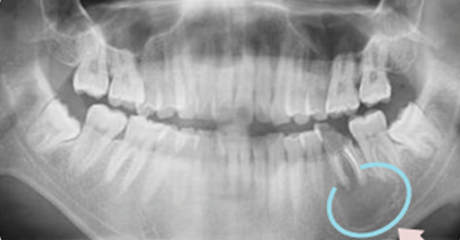

뿌리가 곪으면서 턱뼈 내부에 농 주머니가 생기게 됩니다.